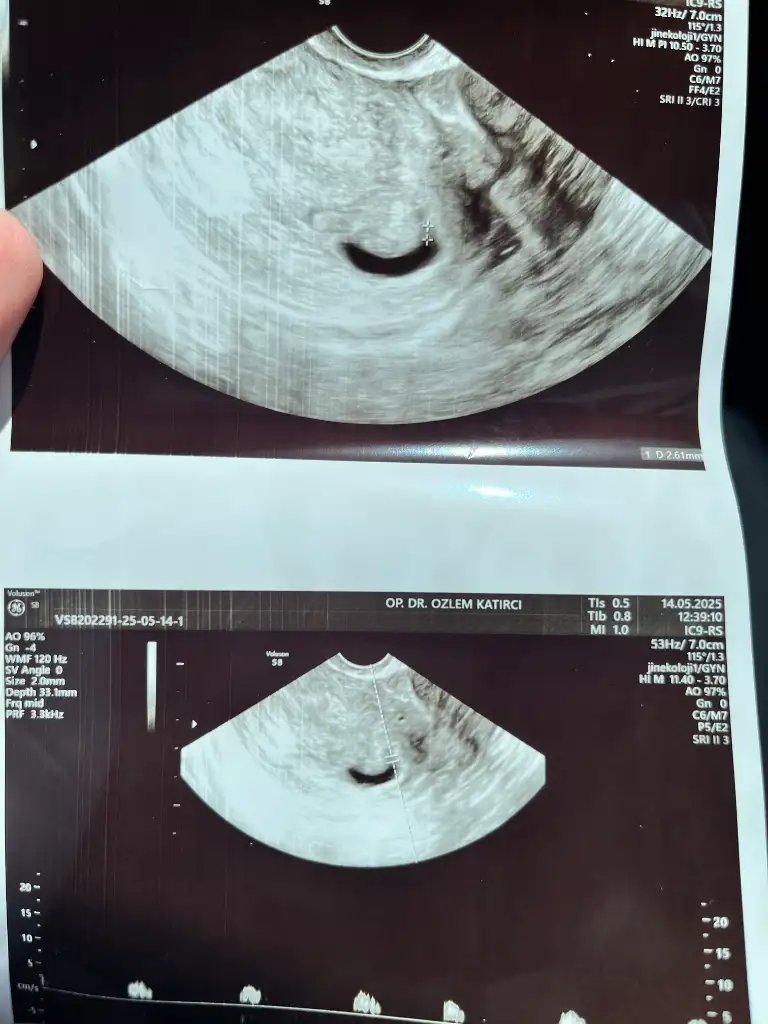

merhaba kızlar 6+5 benimki de ilk fotoğraf Vajinal çekildi ikinci abdominal ikisine de bakar mısınız cinsiyet tahmini ne sizce ☺️

Eklentiler

• IMG_3688.webp

IMG_3688.webp

40 KB · Görüntüleme: 30

• IMG_3685.webp

IMG_3685.webp

21,2 KB · Görüntüleme: 31